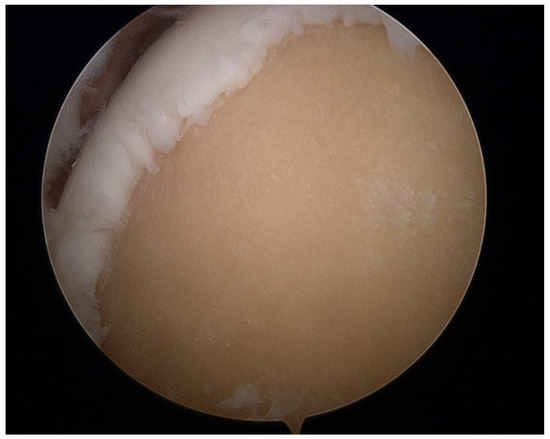

2.2. Surgical Procedure